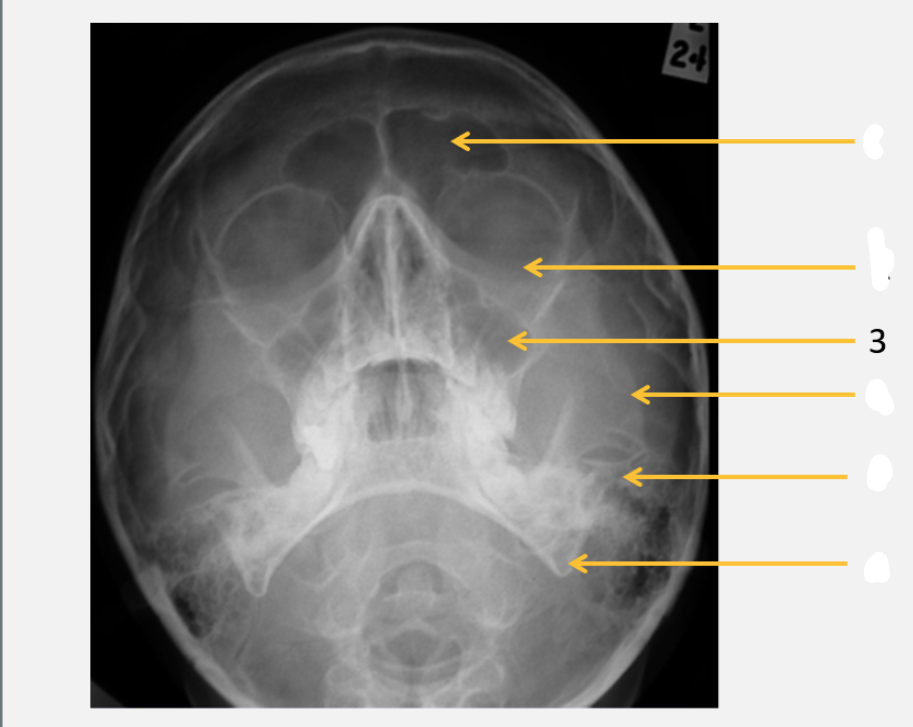

frontal bone

frontal sinus

parietal bone

lambdoid suture

occipital bone

mastoid air cells

Sella turcica

inferior orbital rim

maxillary sinus

zygomatic arch

petrous ridge

angle of mandible